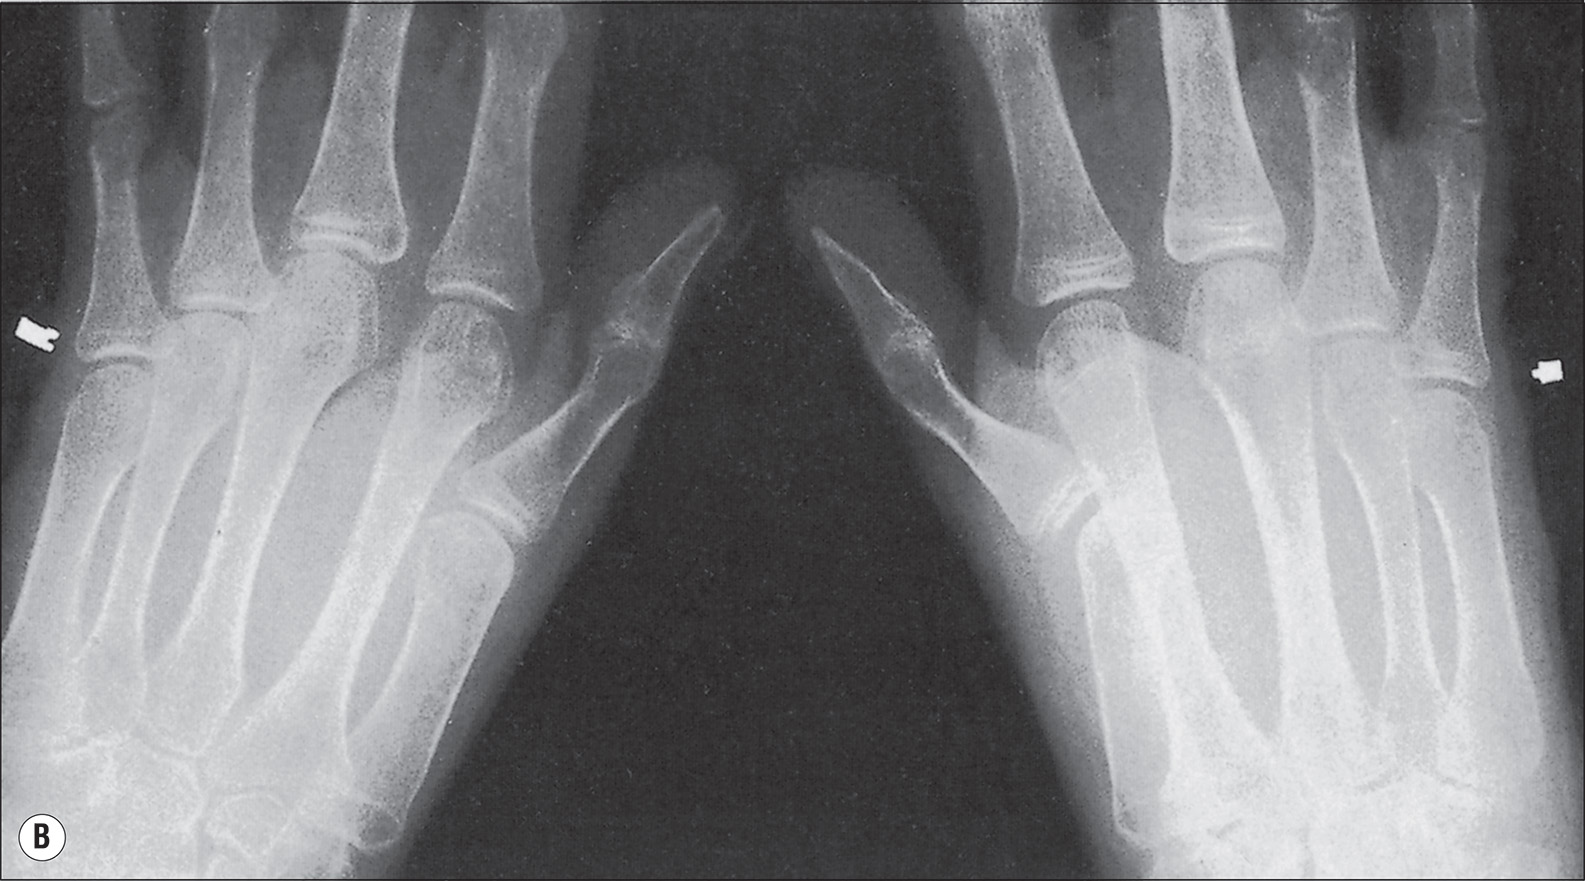

The more extensive the burn and the greater the number of complications, the longer the patient may be confined to bed and relatively immobile. The onset of osteoporosis is accelerated, and its intensity is more marked in the burn illness that features a hypermetabolic state. Klein et al. found that osteoblasts and probably osteocytes underwent apoptosis in response to the glucocorticoid stress hormones. The overall effect of burn is catabolic, and muscle wasting is also noted. If a single extremity of an otherwise normal person is immobilized for a long time because of local trauma, as with a fracture, loss of bone density can be easily seen on plain radiographs. So, with burns isolated to the extremities, the bones of affected extremities become osteoporotic, and in persons with generalized burns, the bones of deeply burned extremities may show more profound mineral loss than is observed in nonburned extremities or in the axial skeleton ( Fig. 41.1 ). This tendency for more osteoporosis in severe burns was also noted by Pandit et al., who found that 56% of postburn patients had radiographic evidence of osteopenia. Van der Wiel et al. found in an x-ray absorptiometry study of 16 adults with fractures of one tibia that there was eventual loss of bone mineral density in the contralateral femur and in the lumbar spine but to a lesser degree than in the ipsilateral femur. These findings, although not strictly analogous to those observed in burns, nevertheless point to the occurrence of generalized osteoporosis in other trauma states and the difference in loss of bone density relative to local factors. In fractures or in burns, impaired mobility and local hyperemia could account for this difference.

(A) At 6 months after injury, the coarsened trabeculation of marked osteoporosis of bones is evident on the left hand and forearm of a 4-year-old boy whose 70% full-thickness burn involved the head, chest, and both upper extremities. (B) A radiograph of the left tibia and fibula obtained on the same date as that of the hand shows minimal atrophy.